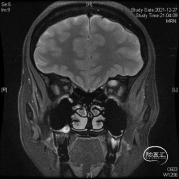

头颅MR体检偶然发现左侧眶尖占位,初步诊断海绵状血管瘤,查体无明显阳性体征。

球后眶尖部位及海绵窦区的病变因为位置深在,周围重要结构众多,对神经外科医生具有极高的挑战性。神经内镜技术发展给我们提供了一条思路。我们通过相关解剖研究发现,病变位于海绵窦外侧壁、颈内动脉外侧、颞极内侧,可选择经眶外侧壁入路;病变位于眶尖内侧,累及海绵窦侧壁,经眶内侧壁入路更为适合;病变主体位于鞍区向一侧海绵窦侧壁侵袭,可以考虑内镜经鼻入路。眶内上壁病变,因为无重要结构,经眶入路最适合!